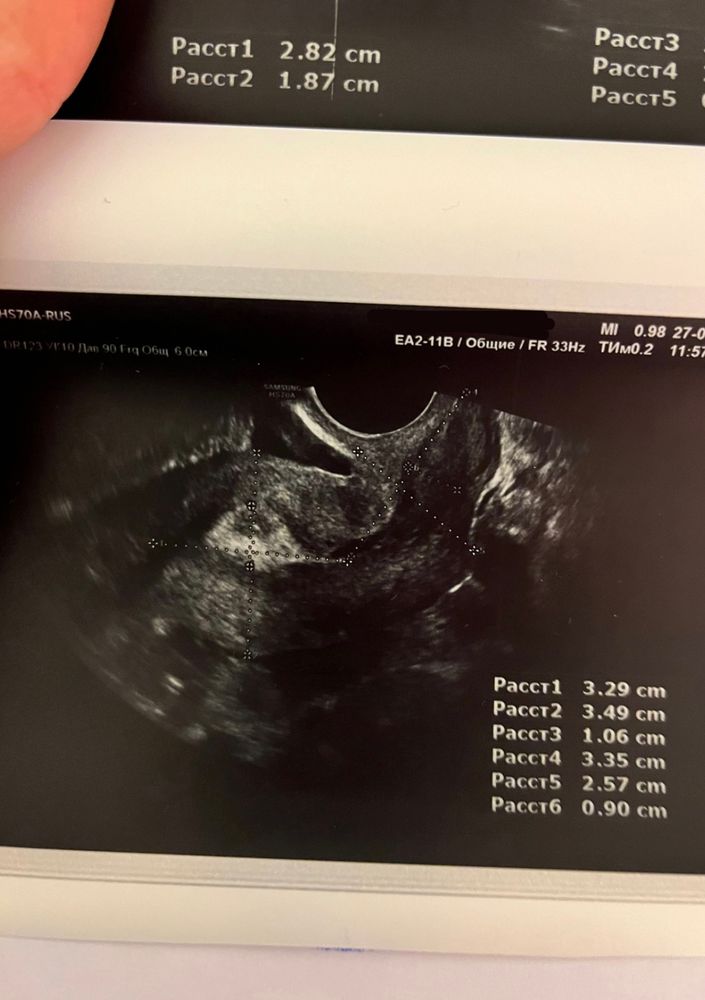

Здравствуйте! Ситуация следующая: с мужем начали практиковать ППА, потому что как говорится бояться уже нечего😂, но прямо планировать ещё рано, только начинаем вставать на ноги. Мы оба госслужащие, поэтому периодически проходим обследования общие, иногда сдаём кровь на ВИЧ, гепатиты. Поэтому за здоровье особо не переживали. М начались 4 марта, закончились 8 марта (всегда идут 4 дня). 3 ППА были с 11 по 13 марта, а 14 марта по моим ощущениям началась О. И вот где-то через неделю начинается самое веселое, частое чувство голода - то есть поем, а через 5 минут такое ощущение, что не ела неделю 🙈 усилилось обоняние, с каждым днём нарастало чувство слабости. Я уже думала, всё, ОНО😍😂 и за неделю (и 2 дня) до начала М начинает тянуть и подергивать левый яичник, иногда потягивает правый. Я пошла на узи малого таза…ожидала услышать что-то конкретное, но врачи сказали наблюдать дальше за состоянием и в случае задержки делать тест, а так, из того, что они увидели: что-то у меня там лопнуло (боюсь неправильно назвать) и произошло кровоизлияние в брюшную полость (большое темное пятно в нижней части, на снимке матки), а боль в левом яичнике обусловлена наличием в нем желтого тела. В общем как-то так. Сейчас уже 4-ый день задержки, левый яичник все также потягивает вечерами, сохраняется слабость и сонливость. Утром сегодня делала тест - кристально чистый, ни намёка на призрака. Подскажите, пожалуйста, в моем случае, я так понимаю, уже можно исключать беременность? Что это может быть? Фото снимков с УЗИ прилагаю (сделаны на 24 ДЦ). Заранее спасибо!